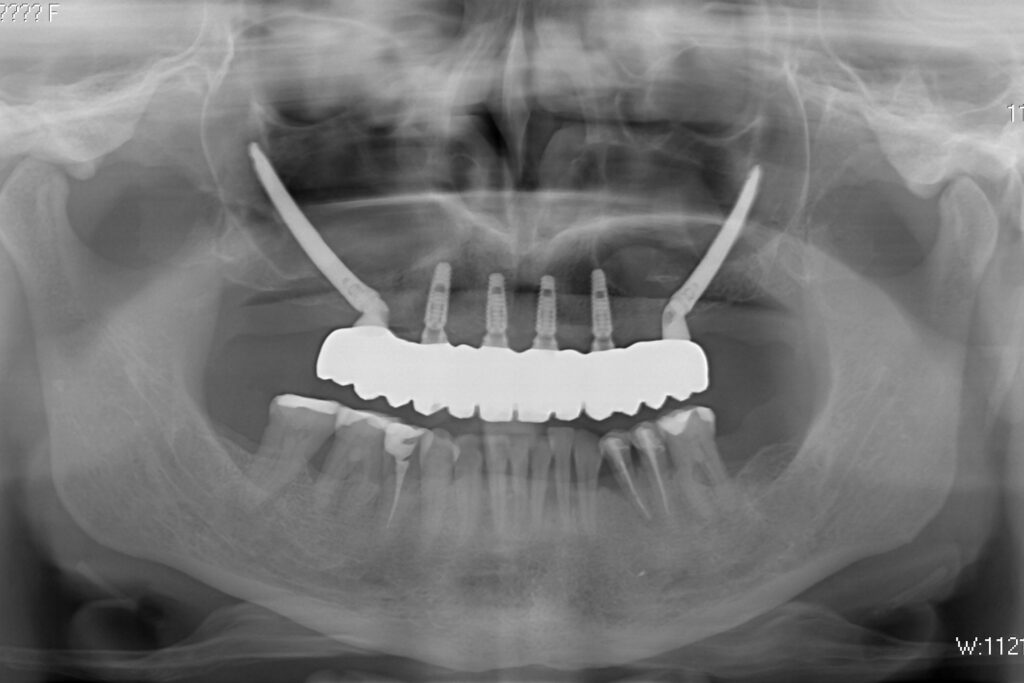

Лечение начато с выбора материала для будущей конструкции (диоксид циркония) и цвета.

Был установлен временный протез из PMMA, максимально воссоздающий форму и цвет (А3) будущей конструкции.

Спустя 20 дней был зафиксирован протез с опопрой на дентальные имплантаты из диоксида циркония.

процесс имплантации